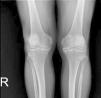

Case presentationForty-six years old male patient presented with history of hip and joint pain for 2 years. His pains were resistant to analgesics. He does not have any comorbidities. He does not have any family history of CPPD or CPPD like symptoms. On laboratory examination C-reactive protein was 2.35mg/L (0–5), serum calcium was 9.2mg/dL (8.6–10.2), magnesium was 1.81mg/dL (1.5–2.6), uric acid was 4.1mg/dL (3.5–7.2), ferritin was 23.5μg/L (30–400), erythrocyte sedimentation rate was 2mm/h (<15), parathormone was 56.82ng/L (15–65), thyroid releasing hormone was: 0.953mU/L (0.27–4.2) and vitamin D was 48ng/mL (20–50). Rheumatoid factor and antinuclear antibodies were negative. HLA-B27, HLA B-51, HLA B52 were negative. There was no history of inflammatory bowel disease and psoriasis. X-rays revealed chondrocalcinosis of the glenohumoral joints, intervertebral disks, acetabular joints, iliac crests, femoral trochanters, iliopubic tuberosities, symphisis pubis, meniscuses, knee joint cartilages, ankles, tarsal joints and heels (Fig. 1). In his magnetic resonance imagining chondrocalcinosis and early coxarthrosis was seen in bilateral hip joints. There was not any sign of sacroiliac inflammation. He was refractory to multiple NSAIDs, colchicine, sulfasalazine, methotrexate and low-middle dose corticosteroid. Subcutaneous adalimumab 40mg was started each 2 weeks. Methotrexate and 2mg dexamethasone treatments continued. A major reduction of pain was observed in his 3 months follow-up. No side effects of adalimumab were observed. The patient's follow-up continues stably under anti-TNF therapy.